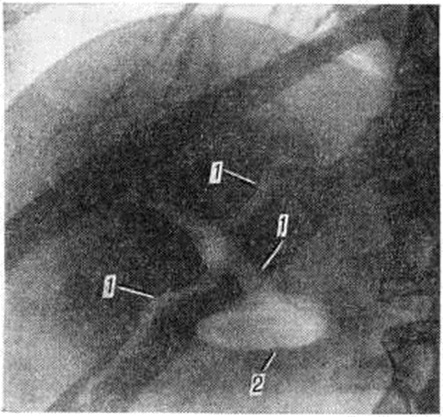

Диагноз наружного Жёлчные свищи обычно устанавливается без труда на основании истечения из свища желчи (смотри полный свод знаний), однако определить с достоверностью, откуда исходит свищ, удаётся после рентгенологическое исследования (рисунок 1). Одним из самых простых и информативных методов является фистулография (смотри полный свод знаний), позволяющая получить ценные данные.

Рис. 1.

Фистулограмма неполного наружного желчного свища: 1 — свищевой канал (остаток пузырного протока), контрастированный через дренажную трубку (на рисунке трубка слева); 2 — камень в общем желчном протоке.